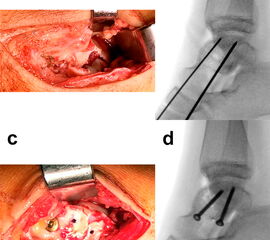

Frakturen des Proc. posterior tali und Trümmerfrakturen des hinteren Anteils des Taluskorpus (Abb. 14), die vorwiegend bei komplexen Fußverletzungen anzutreffen sind, erfordern zur Reposition und Osteosynthese aufgrund ihrer Morphologie und anatomischen Lage einen posterolateralen oder (selten) posteromedialen Zugang 4. Der Zugang liegt parallel zur Achillessehne. Im Subkutangewebe ist der N. suralis zu schonen, welcher die Faszie auf Höhe der Mittellinie durchbricht und dann nach lateral zieht. Nach Eröffnen der oberflächlichen und tiefen Faszie werden Muskelbauch und Sehne des M. flexor hallucis longus unter Schonung des medial davon verlaufenden posterioren Gefäß-Nerven-Bündels nach medial beiseite gehalten.

Der Einsatz eines Femurdistraktors, welcher zwischen Tibia und Calcaneus aufgespannt wird, kann zur Übersicht über das obere und untere Sprunggelenk sehr hilfreich sein. Die anatomische Gelenkreposition und temporäre Fixierung erfolgen unter direkter Sicht. Zur Osteosynthese kommen meist Schrauben zum Einsatz (Abb. 14). Auf eine Irritation der Gelenkflächen oder der Flexor-hallucis-longus-Sehne sollte bei Einbringen der vorzugsweise kleinkalibrigen (2,7 – 3,5 mm) Schrauben geachtet werden 4.